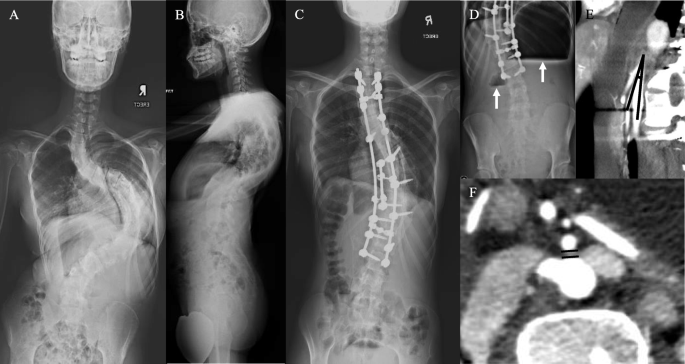

One case with superior mesenteric artery (SMA) syndrome after scoliosis surgery (preoperative x-ray – a & b, postoperative AP x-ray – c). Sagittal (d) and axial (e) of computed tomography angiography (CTA) of the abdomen revealed aortomesenteric angle of 10°, SMA-aorta distance of 3.2 mm and constriction of 3rd part of duodenum by the branches of the SMA

Another case with superior mesenteric artery (SMA) syndrome after scoliosis surgery (preoperative x-ray – a & b, postoperative AP x-ray – c) Erect abdominal radiograph (d) showed double bubble sign (white arrows). Sagittal (e) and axial (f) of CTA of the abdomen revealed an Aortomesenteric angle of 10° and SMA-aorta distance of 2.6 mm. Clinical assessment, MRI whole spine and CT thoracolumbosacral did not show any secondary causes for scoliosis